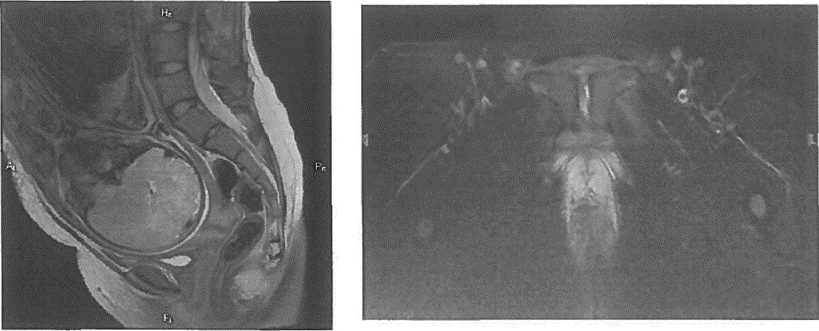

МР-пельвиметрия - магнитно-резонансная пельвиметрия, измерение размеров полости таза с помощью магнитно-резонансной томографии.

Низкий рост, уменьшение межвертельного размера таза, поперечного и продольного размеров пояснично-крестцового ромба Михаэлиса, отношение роста беременной к высоте дна матки = менее 4,7 значимо чаще встречаются при клинически узком тазе [9], [10], [11], [12], [13]. Поэтому их измерение используют в качестве скринингового метода при его прогнозировании [14], [15]. Данные компьютерной томографии показали, что женщины с уменьшенным прямым размером выхода таза и узким лонным углом имеют повышенные риски затрудненных родов, требующих оперативного родоразрешения [16]. В современной клинической практике в качестве дополнительного объективного метода оценки размеров полости таза используют магнитно-резонансную пельвиметрию, которая не оказывает лучевой нагрузки [17], [18].

Комментарий. МР-пельвиметрия является радиационно-безопасным, объективным методом оценки размеров полости таза. При этом степень уменьшения размеров таза по данным МРТ обратно пропорциональна частоте кесарева сечения, влагалищных родоразрешающих операций и травм промежности [60], [61]. Применение МР-пельвиметрии целесообразно в группе риска, показания к ее проведению определяются по результатам клинического обследования (см приложение). Рутинное применение МРТ не рекомендуется, так как не является методом выделения группы женщин, подлежащих дородовому оперативному родоразрешению [62].

• Рекомендовано женщинам, у которых по заключению консультативного осмотра в КДЦ акушерского стационара третьего уровня определены показания к уточнению размеров таза для выбора способа родоразрешения, проводить МР-пельвиметрию [17], [18], [59].Уровень убедительности рекомендаций В (уровень достоверности доказательств - 3).